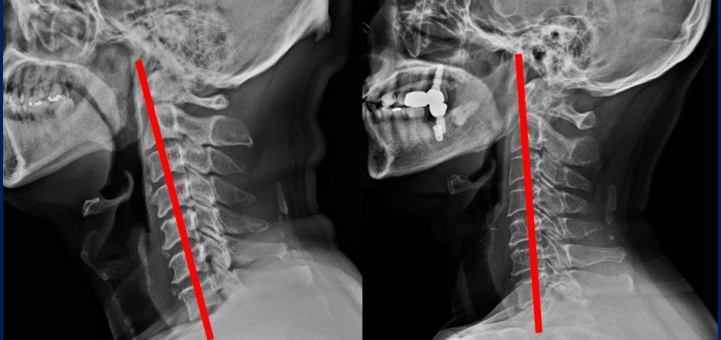

거북목/일자목은 잘못된 자세로 목이나 어깨의 근육이 늘어나 통증이 생기는 증상을 말합니다. 거북목 /일자목의 가장 큰 원인은 평소에 컴퓨터 모니터를 많이 보는 사람, 특히나 낮은 위치에 있는 모니터를 내려다보는 사람에게 많이 발생하고, 책을 보는 자세에서도 유발될 수 있습니다. 거북이가 목을 뺀 상태와 비슷하여 거북목증후군이라는 이름이 붙여졌습니다.

고개가 1cm 앞으로 빠질 때마다 목뼈에는 5kg씩 하중(무게)이 증가하여 심할 경우에는 마치 목 위에 20kg 정도 되는 물건이 올라가 있는 것과 같은 부담을 지니게 됩니다.